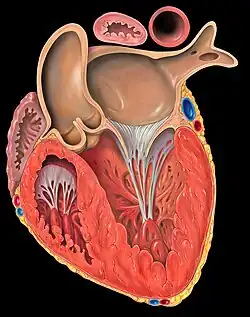

Coupe frontale du ventricule gauche du cœur humain.

Coupe frontale du ventricule gauche du cœur humain. Les principales parties du cœur.

Le cœur est un muscle creux contenant deux parties séparées bien qu'accolées l'une à l'autre : le « cœur gauche » et le « cœur droit ». Ces deux « cœurs » sont situés côte-à-côte dans l'axe base-apex, séparés par une paroi globalement verticale et orientée dans l'axe du cœur. Chacune de ces deux parties est subdivisée en deux chambres ou cavités, l'atrium (ou oreillette) vers la base et le ventricule vers l'apex. Ces deux cavités sont séparées par une valve ; on distingue ainsi la valve mitrale, entre l'atrium et le ventricule gauches, et la valve tricuspide, entre l'atrium et le ventricule droits. L'organisation est symétrique entre le cœur gauche et le cœur droit, bien que le cœur gauche soit plus volumineux. Afin que le ventricule droit puisse répondre à ses contraintes de pression dilatatrice, la trabécule septo-marginale solidarise les différentes parois ventriculaires[2].

La paroi séparant les cavités gauche et droite est appelée septum. On distingue le septum interventriculaire entre les ventricules gauche et droit, le septum interatrial entre les atriums gauche et droite, et le septum atrioventriculaire entre les atriums et les ventricules. La terminologie ne doit pas être source de confusion vis-à-vis des positions relatives ; en effet, du fait de l'axe globalement oblique vers la gauche, le cœur gauche est grossièrement situé en arrière et à gauche du cœur droit, exception faite de l'apex, principalement constitué de l'extrémité du cœur gauche.

Système valvulaire

Le système valvulaire est composé des quatre valves cardiaques séparant les différentes cavités et empêchant le sang de refluer dans le mauvais sens. Il existe la valve tricuspide, la valve aortique , la valve pulmonaire et la valve mitrale.